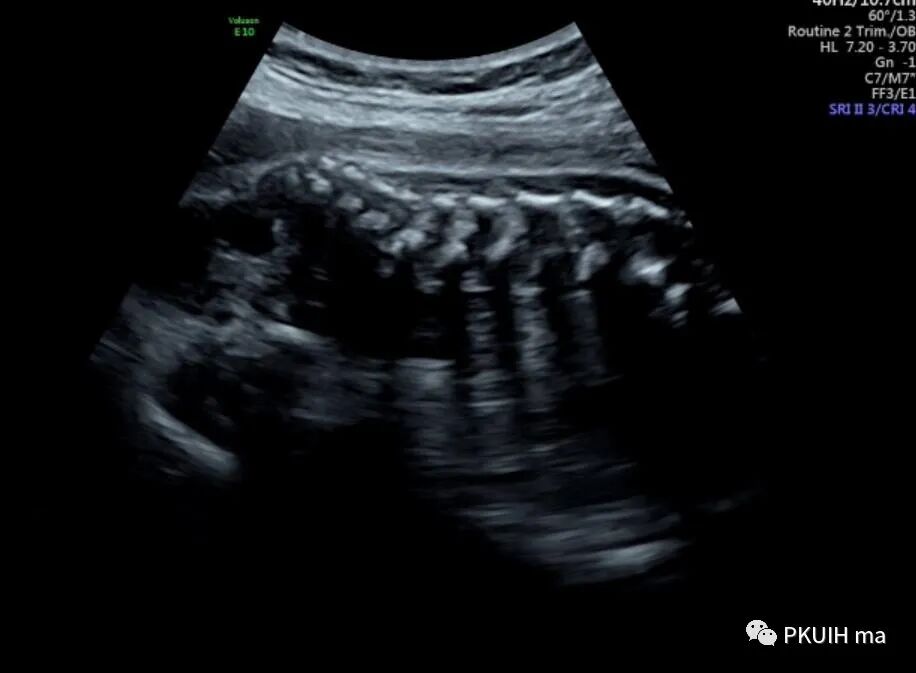

胎儿骶尾部结构清晰、未见明确占位性病变